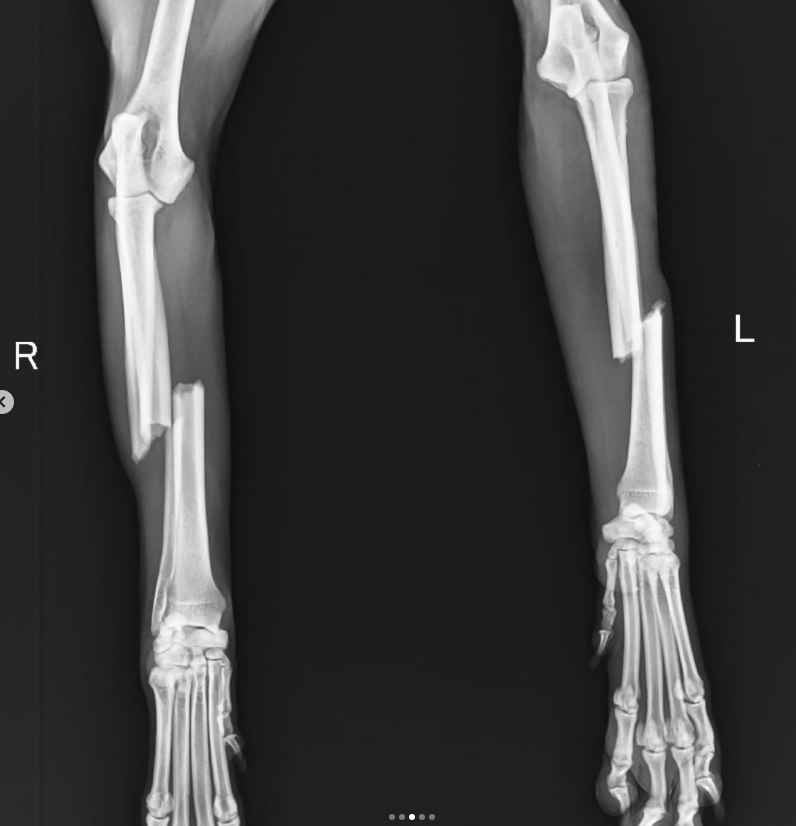

Nova is going to go in for surgery today. The breaks in his leg need plating and implants…they won’t fix with just splints.

The surgery is costing us Rs.25000 per leg.

If you look at slide 3 you can see how bad the breaks are. I can’t even imagine the pain he is in. ๐ And yet he’s so cooperative and wags his tail..